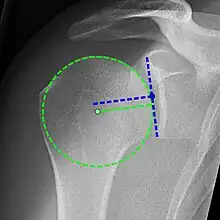

High-riding humeral head in a rotator cuff tear.

X-ray projectional radiography cannot directly reveal tears of the rotator cuff, a 'soft tissue', and consequently, normal X-rays cannot exclude a damaged cuff. However, indirect evidence of pathology may be seen in instances where one or more of the tendons have undergone degenerative calcification (calcific tendinitis). The humeral head may migrate upwards (high-riding humeral head) secondary to tears of the infraspinatus, or combined tears of the supraspinatus and infraspinatus.[47] The migration can be measured by the distance between:

• A line crossing the center of a line between the superior and inferior rims of the glenoid articular surface (blue in image).

• The center of a "best-fit" circle positioned over the humeral articular surface (green in image)

Normally, the former is positioned inferiorly to the latter, and a reversal is therefore indicating a rotator cuff tear.[47] Prolonged contact between a high-riding humeral head and the acromion above it, may lead to X-rays findings of wear on the humeral head and acromion and secondary degenerative arthritis of the glenohumeral joint (the ball and socket joint of the shoulder), called cuff arthropathy, may follow.[46] Incidental X-ray findings of bone spurs at the adjacent acromioclavicular joint may show a bone spur growing from the outer edge of the clavicle downwards towards the rotator cuff. Spurs may also be seen on the underside of the acromion, once thought to cause direct fraying of the rotator cuff from contact friction, a concept currently regarded as controversial.